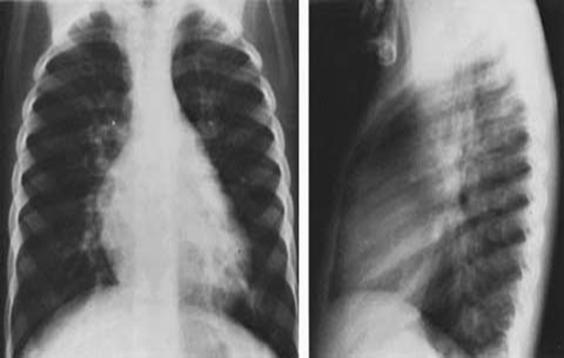

c.RX.

-cardiomegalie cu largirea AD si VD

-Bonbarea arcului AP

-semne de circ pulmonara crescuta